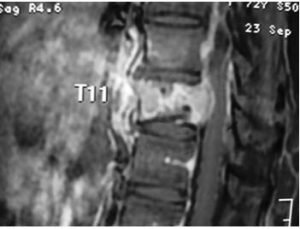

Madam B, a 72-year-old female, presented to my clinic recently with 3 months history of low back pain radiating to her left supra-iliac region. Her symptoms had worsened progressively. She had tenderness elicited by lumbar spine flexion. Neurological examination of her lower limbs was normal. X-ray and MRI of her spine revealed an extensive infiltrative lesion of T11 vertebral body, and its left pedicle. The posterior wall of the vertebra was eroded, and the lesion was encroaching onto the spinal cord and compressing it. The assessment was an extensive T11 spinal metastasis with cord compression and high risk of pathological fracture that could result in paralysis. Madam B underwent T11 decompression laminectomy with clearance of tumor tissue immediately surrounding the cord. The spine was instrumented from T8 to L1 segments to provide stability and to pre-empt pathological fracture. Frozen section of the specimen taken during surgery indicated the lesion to be lymphoma. This was later sub-typed as diffuse large B-cell lymphoma. Her back pain resolved completely following the surgery and she was ambulating well. She was referred to hematologist for outpatient chemotherapy treatment which started one week following the surgery.

There are potential pitfalls in the diagnosis of spinal metastasis. Spinal metastasis may not be suspected because it is a less common cause of back pain. Metastatic lesions may not be obvious on X-Ray until extensive bone destruction has taken place. Hence a strong index of suspicion is needed to pick up the diagnosis early. When diagnosis is suspected, MRI is the most useful investigation to demonstrate the extent of the lesion and the state of cord compression. Bone scan is useful to search for other sites of bone involvement. PET scan is useful to demonstrate sites of another organ metastasis. Histological diagnosis of specimens obtained through percutaneous biopsy or open surgery is ultimately needed for guiding treatment.